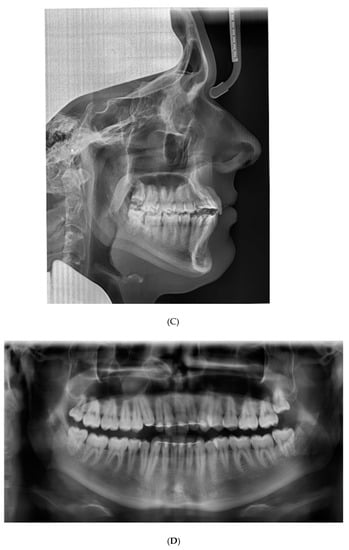

Figure 3A shows the case at the first presentation. The photographs demonstrate that the 13 shows excessive palatal root torque, and the 23 shows excessive buccal root torque. A cant of the upper incisors can be observed. Moreover, cross-bites are present between the 14 and the 44 and between the 23 and the 34.

The patient presented with a Class I profile and a chin point deviation to the right side (Figure 3A). The intra-oral assessment showed good oral hygiene, a thin gingival biotype, group function on the left and right side, and fixed retainers (0.0195-inch, 3-strand, heat-treated twist wire, Wildcat, GAC International, Bohemia, NY, USA) in the upper anterior segment and lower anterior segment (Figure 3A). The dental cast assessment showed a Class I molar and canine occlusion, an overjet of 2 mm, and an overbite of 3 mm. A cant of the upper incisors was present with palatal root torque of the 13 and buccal root torque of the 23. Crossbites were present between the 14/44 and the 23/34. The arch length discrepancy measurement resulted in values of 0 mm in the case of the maxillary arch and −4 mm in the case of the mandibular arch. No tooth size discrepancy was present. The PAR index resulted in a score of 12 points [22] (Figure 3B). The lateral cephalometric radiograph showed a Class I intermaxillary relationship with an ANB angle of 3.2° (VistaPano S Ceph, Dürr Dental imaging software, Dürr Dental SE, Bietigheim-Bissingen, Germany) (Figure 3C). The panoramic radiograph (VistaPano S Ceph, Dürr Dental imaging software, Dürr Dental SE, Bietigheim-Bissingen, Germany) showed a maxillary sinus mucosal cyst (MSMC) on the right side and external apical root resorption located at the 12, 11, and 21 (Figure 3D).

Figure 3. Documentation before orthodontic re-treatment. (A) Extra-oral and intra-oral photographs. (B) Dental casts. (C) Lateral cephalometric radiograph. (D) Panoramic radiograph.